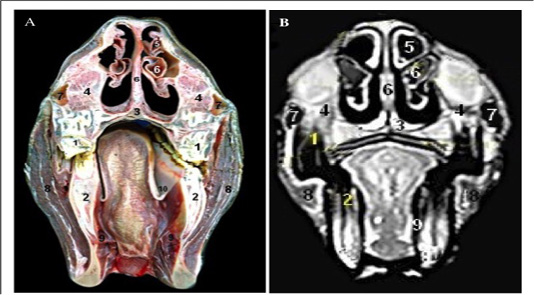

Cross sectional anatomy (Panel A) and MR image (Panel B) of horse head at the level of upper and lower incisors. 1) Upper incisors teeth; 2) Lower incisors teeth; 3) plate of alar cartilage; 4) Horn of alar cartilage; 5) Hard palate; 6) Oral cavity proper; 7) Apex of tongue; 8) Labial vestibule; 9) Apical naris dilatator muscle; 10) Mentalis muscle.

Cross sectional anatomy (Panel A) and MR image (Panel B) of horse head at the level of body of mandible. 1) Body of mandible; 2) Nasal bone; 3) Maxilla bone; 4) medial accessory nasal cartilage at Alar fold; 5) Straight fold; 6) Basal fold; 7) False nostril (Nasal diverticulum); 8) Vomeronasal organ; 9) Tongue; 10) Buccinators muscle; 11) Sublingual recess.